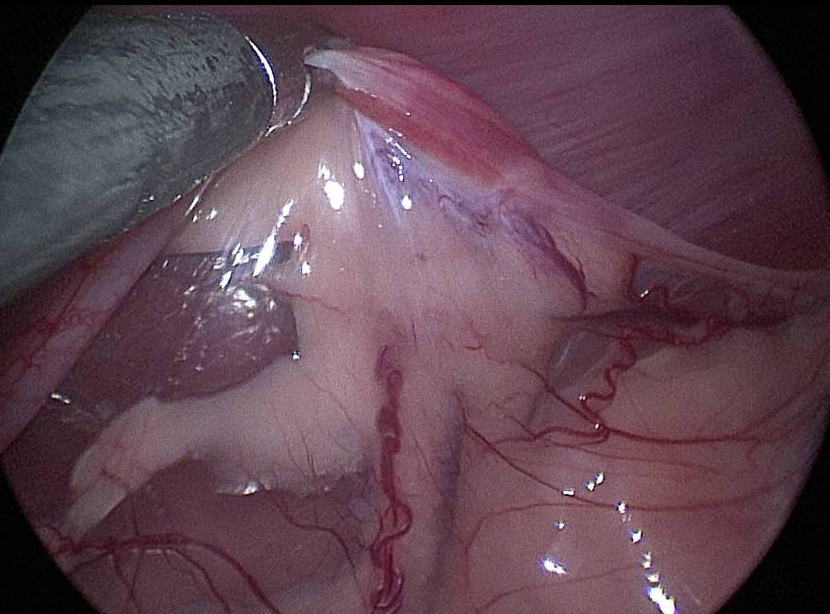

The public is learning more about the massive benefits of minimally invasive, image-guided procedures in VetMed! #MIIPs #IRad "Veterinary Endoscopy Market worth 219.0 million USD by 2023" shar.es/a0qo2S @OVCsinghlab